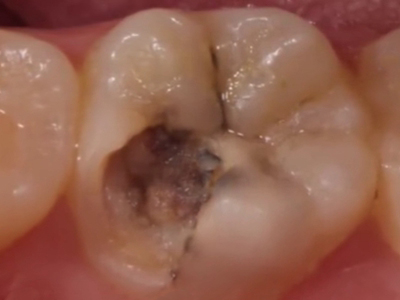

年轻恒牙龋指的是儿童萌出不久的第一恒磨牙龋病和上颌恒切牙龋病,其中第一恒磨牙龋病占年轻恒牙龋的90%,发病早,进展快,可表现为白垩色斑片、点隙窝沟墨浸状龋坏或龋洞。本病的发生和年轻恒牙的特点以及儿童饮食、口腔卫生等因素有关。

年轻恒牙龋好发于第一、二恒磨牙(牙合)面、邻面,上颌中切牙邻面,多为急性龋,龋坏进展快。平滑面的早期龋多为白垩色的斑片,点隙窝沟的早期龋多为浸墨状,表面粗糙。如果早期龋不及时治疗,可逐渐形成大而深的龋洞,易导致牙髓炎和根尖周炎。